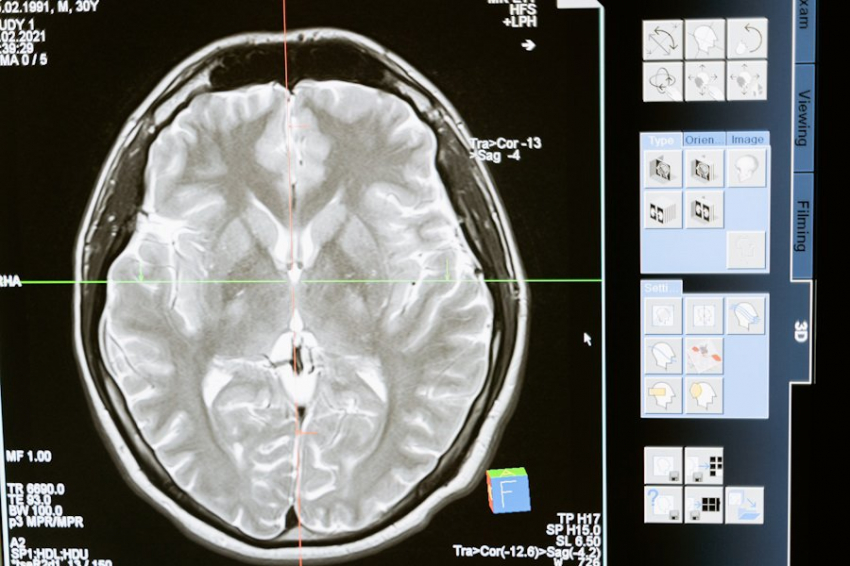

Биомедицинские инженеры из Мельбурнского университета изобрели систему 3D-печати, или биопринтер, способный изготавливать структуры, которые точно имитируют различные ткани человеческого тела: от мягкой мозговой ткани до более твердых материалов, таких как хрящи и кости. Исследование опубликовано в журнале Nature.